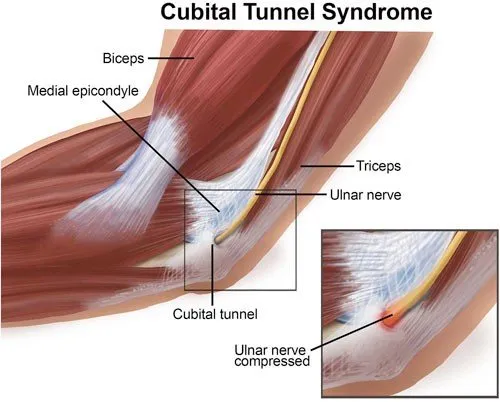

Ulnar Nerve Compression (Cubital Tunnel Syndrome)

Wear-and-tear or inflammatory conditions causing pain, stiffness, and reduced motion.